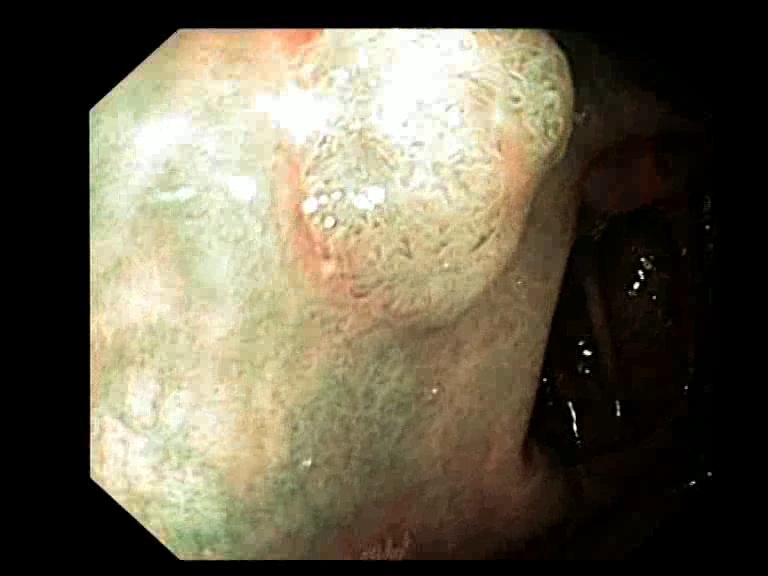

Figure 3: Key-frames obtained by our method and their corresponding depth maps. The polyp is visible from different viewing angles in these selected frames.

The selected key-frames are finally used to reconstruct the 3D surface of the polyp. We have used Facebook’s 3D image GUI to view the reconstructed polyp surface, the link to the video is shown here: https://youtu.be/PJKfk0Mqu2I\href https://youtu.be/PJKfk0Mqu2I. 3D visualization of a polyp helps in surgeries involving the removal of the polyp from its root. This gives better visualization of polyps for diagnosis. Fig. 3 shows some of the results of key-frame extraction and the corresponding depth maps. No publicly available datasets or methods using them that predict depth maps from endoscopic frames exist. Thus, a comparison between different methods for predicting depth from endoscopic images couldn’t be performed.